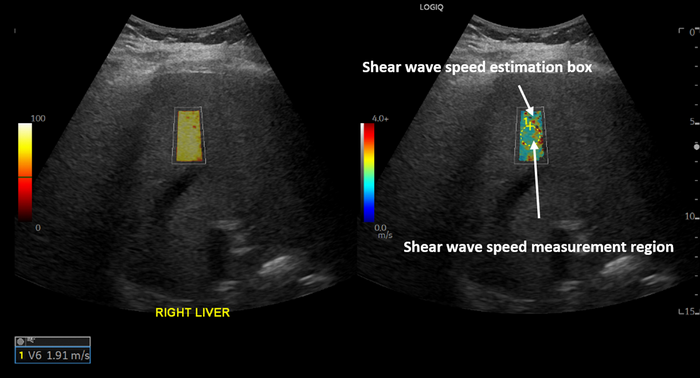

In the retrospective study, the researchers compared liver stiffness of patients with a history of COVID-19 infection to two control groups. All patients underwent ultrasound shear wave elastography between 2019 and 2022 at Massachusetts General Hospital. Shear wave elastography is a specialized technique that uses sound waves to measure the stiffness of tissue.

The patients were categorized into one of three groups based on when they underwent elastography and whether they tested positive for COVID-19. The COVID-19 positive group contained 31 patients who had a positive COVID-19 PCR test result at least 12 weeks before the elastography exam. The pandemic control group consisted of a random sample of 50 patients who underwent elastography during the COVID-19 pandemic and had a history of only negative COVID-19 PCR test results. The pre-pandemic control group consisted of a random sample of 50 patients who underwent an elastography exam prior to the COVID-19 pandemic.

After controlling for age, sex and time period, a statistical analysis of the elastography results revealed that COVID-positive patients had a statistically significant higher liver stiffness than the control patients.

COVID-positive patients had a higher median live stiffness (7.68 kPa) than pandemic control patients (5.99 kPa).